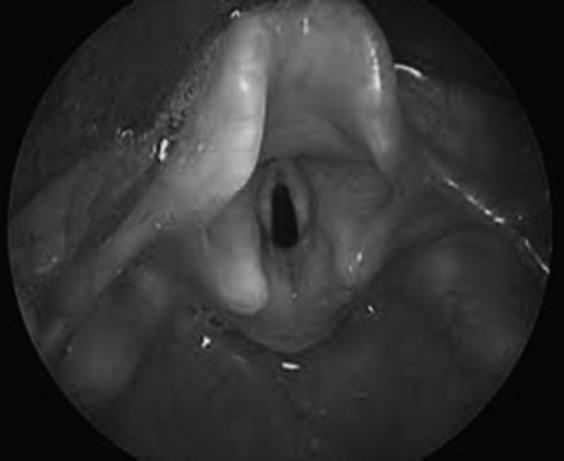

6. O passo mais importante é a visualização das cordas vocais (Figura 6.1.1):

Figura 6.1.1 – Visualização das cordas vocais (figura a cores na página do livro em https://materiais.lidel.pt/neonatologia_procedimentos_tecnicos).

9. Levantar a lâmina do laringoscópio para abrir a boca e, simultaneamente, inclinar ligeiramente a ponta da lâmina para elevar/pinçar a epiglote e visualizar a glote (Figura 6.1.4).